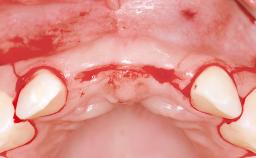

A 38-year-old woman presented with an esthetically unacceptable fixed partial denture replacing teeth 11, 21, 22. She had lost these teeth due to trauma when she was a child. The patient was not in pain but very concerned based on her previous experience that dental treatments had never satisfied her esthetic expectations. She was in good general health and reported no regular medications. No periodontal disease was noted despite the fact that the buccal flange of the prosthesis impeded cleaning of the tooth abutments. The patient did not smoke and complied with home maintenance requirements, as evidenced by her good oral hygiene status.